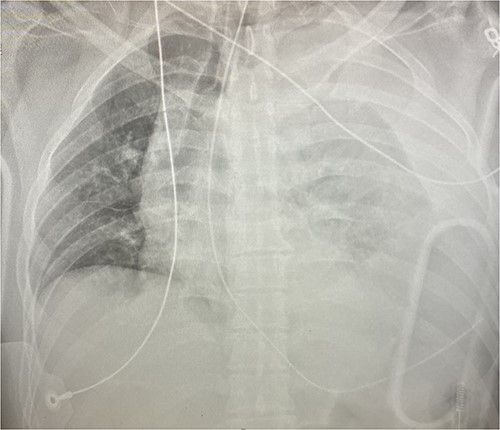

An approximately 40-year-old male was involved in a motor vehicle collision after hitting a concrete wall at highway speeds. The patient was found to have a Glasgow Coma Scale (GCS) score of 3 on scene, so he was intubated and brought to the trauma center as a level I trauma activation via helicopter. Upon arrival, his primary survey was significant for an airway secured with an endotracheal tube, tachycardic to the 110 s, hypotensive with a systolic in the 60s and GCS of 3 T. His secondary survey identified an open mandibular fracture, right hip dislocation and an obvious left thigh deformity with palpable distal pulses. His chest x-ray revealed a left hemothorax (see Fig. 1), his pelvic-x-ray confirmed the hip dislocation, and his Focused Assessment with Sonography for Trauma (FAST) examination was negative for free fluid in all four windows. A left thoracostomy tube was immediately placed, which evacuated 500 cc of blood with minimal continuous output. He was given 1 unit of packed red blood cells (PRBC) with blood pressure normalization but persistent tachycardia.